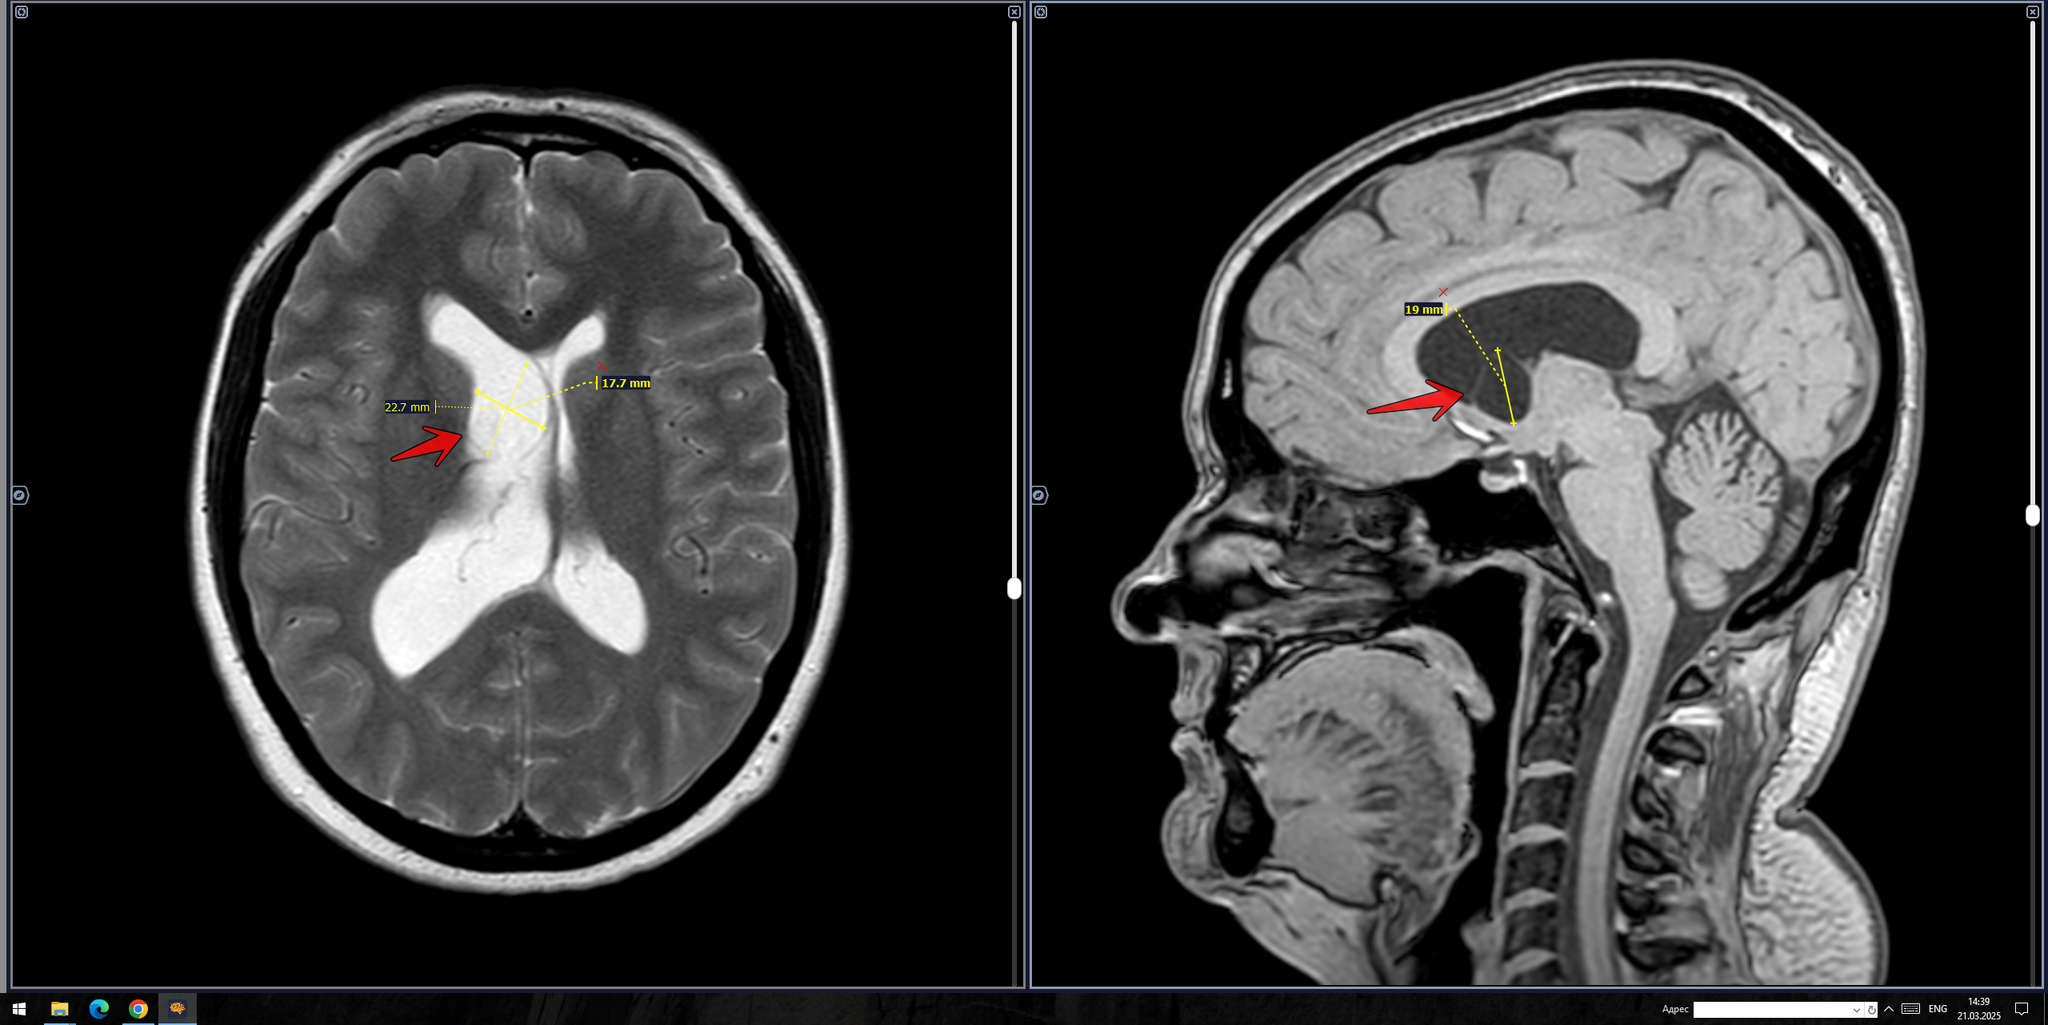

Атерома мрт

Атерома мрт 113 фото